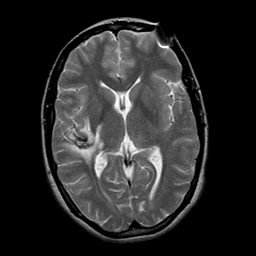

overlay -- Slice #14

[Home][Help][Clinical] Slice 14

Click on sagittal image to select slice. Click on thin tickmark to change timepoint, or thick tickmark for overlay.